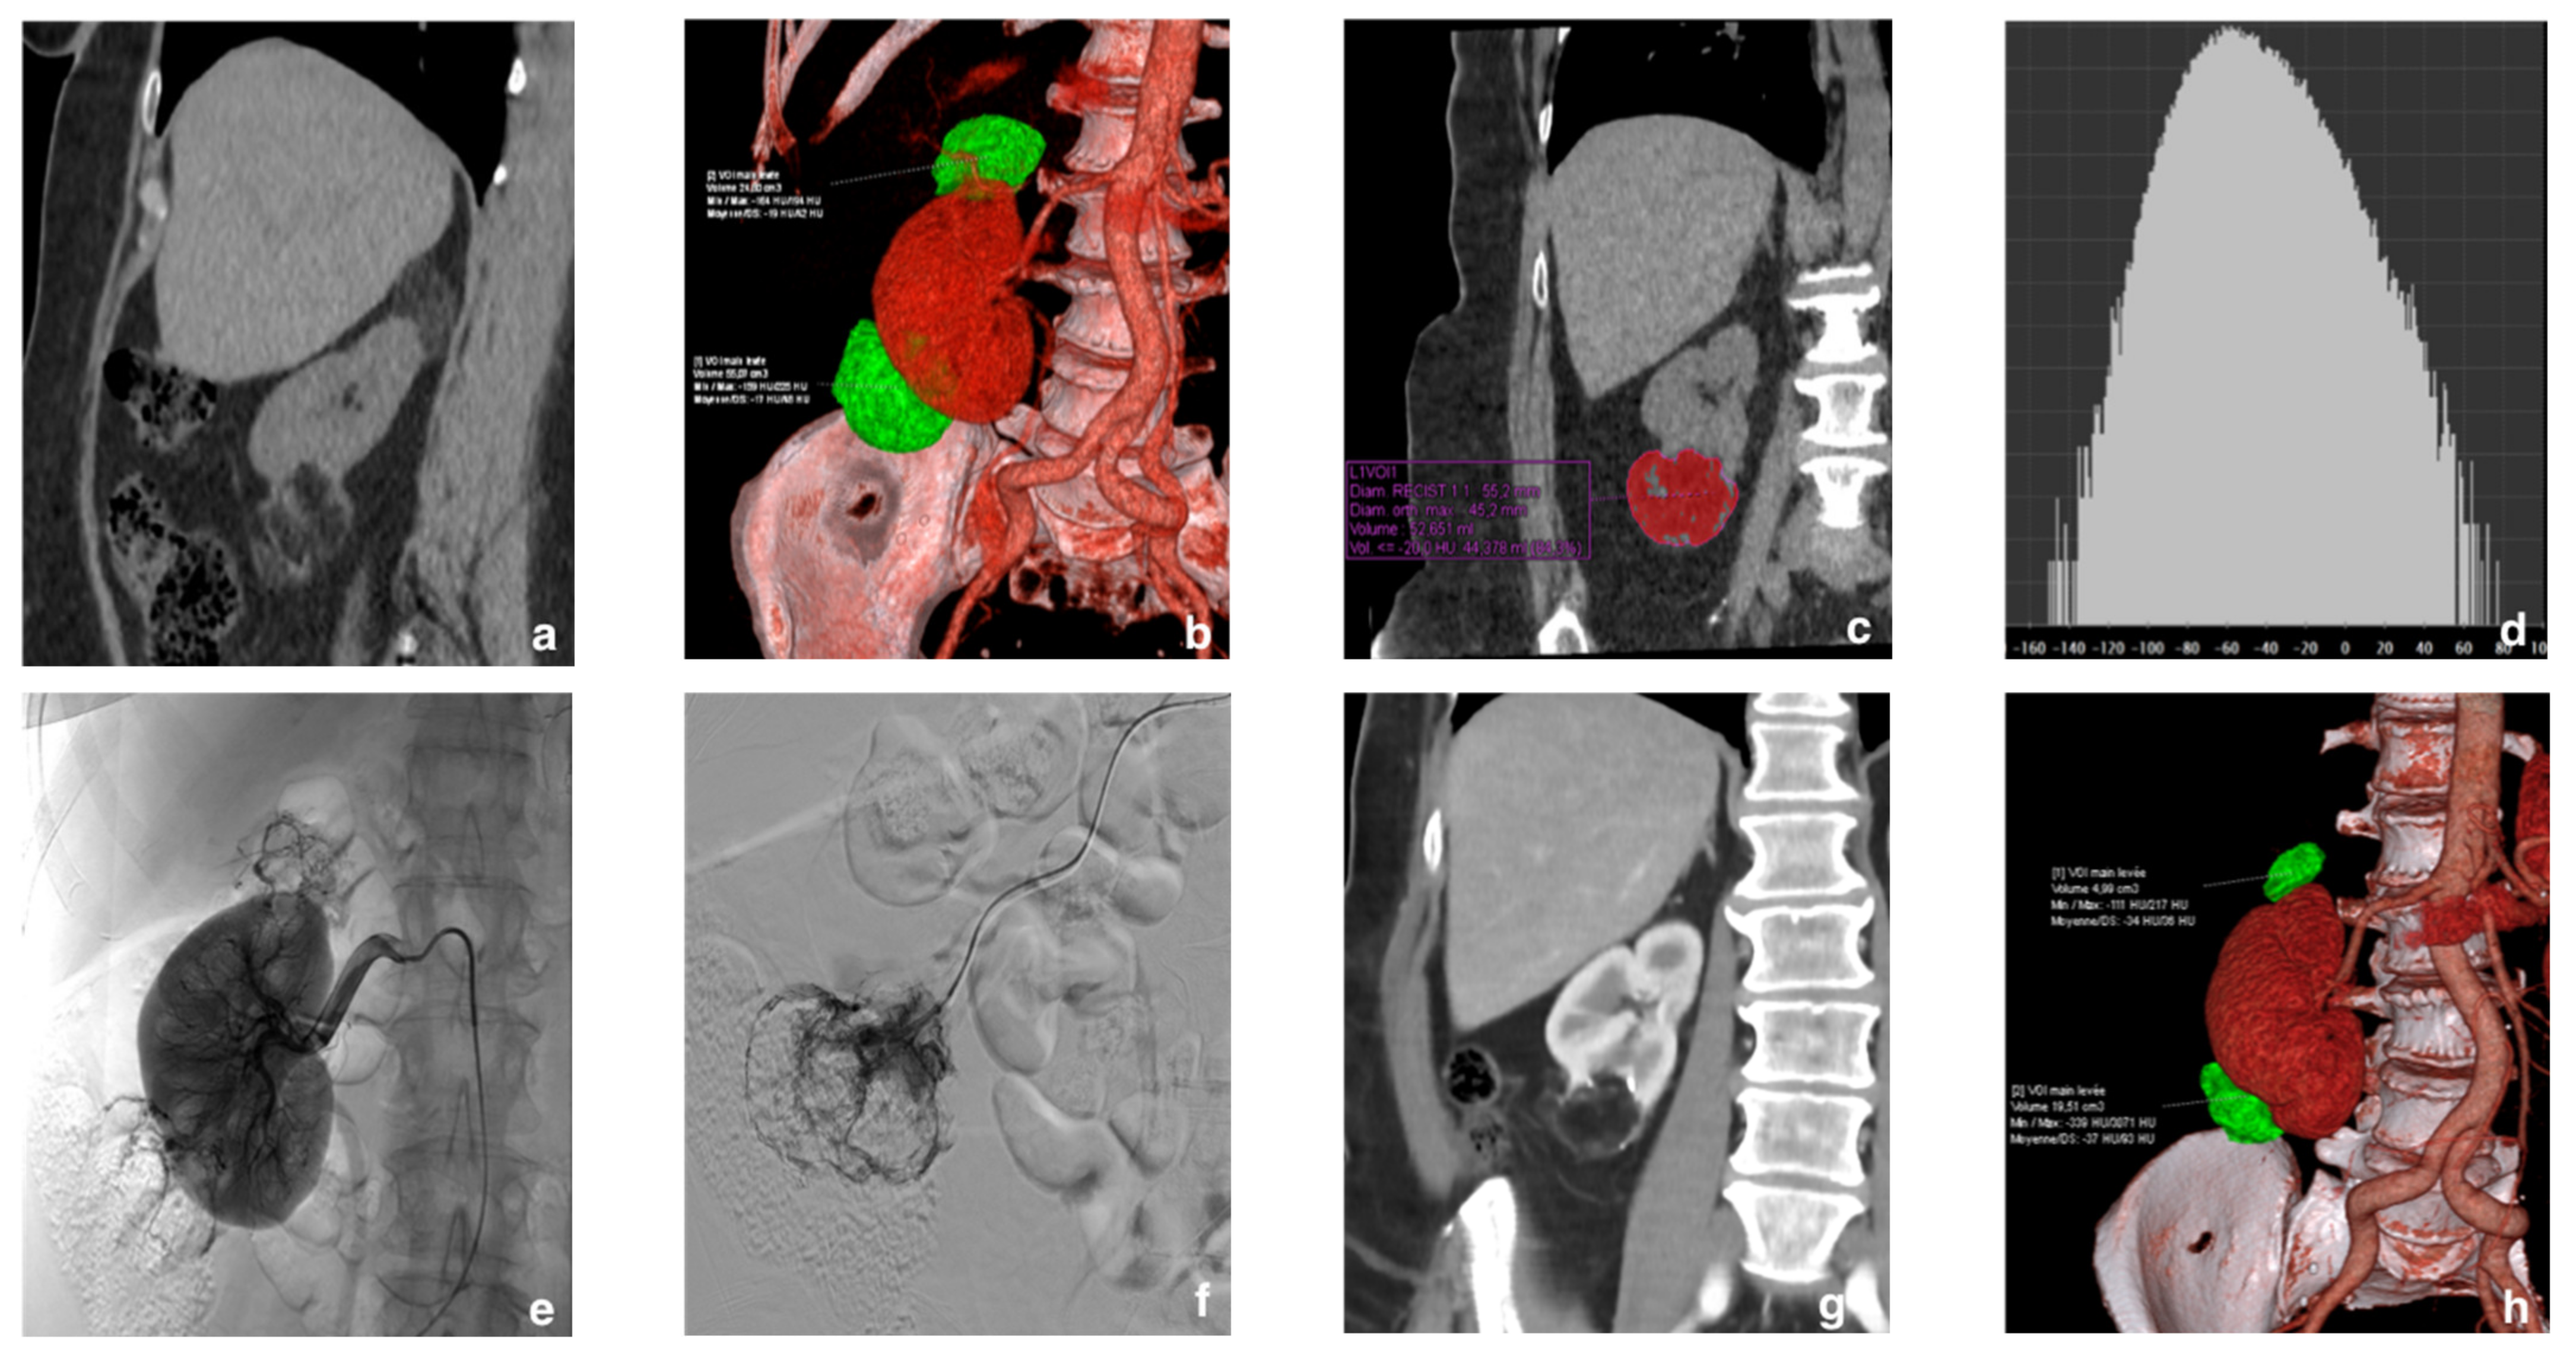

2.2. Diagnosis and Tumor Size

2.3. Selective Arterial Embolization (SAE)

2.4. Follow-Up

3.2. Selective Arterial Embolization (SAE)

- Planché, O.; Correas, J.M.; Mader, B.; Joly, D.; Méjean, A.; Hélénon, O. Prophylactic embolization of renal angiomyolipomas: Evaluation of therapeutic response using CT 3D volume calculation and density histograms. J. Vasc. Interv. Radiol. 2011, 22, 1388–1395. [Google Scholar] [CrossRef] [PubMed]